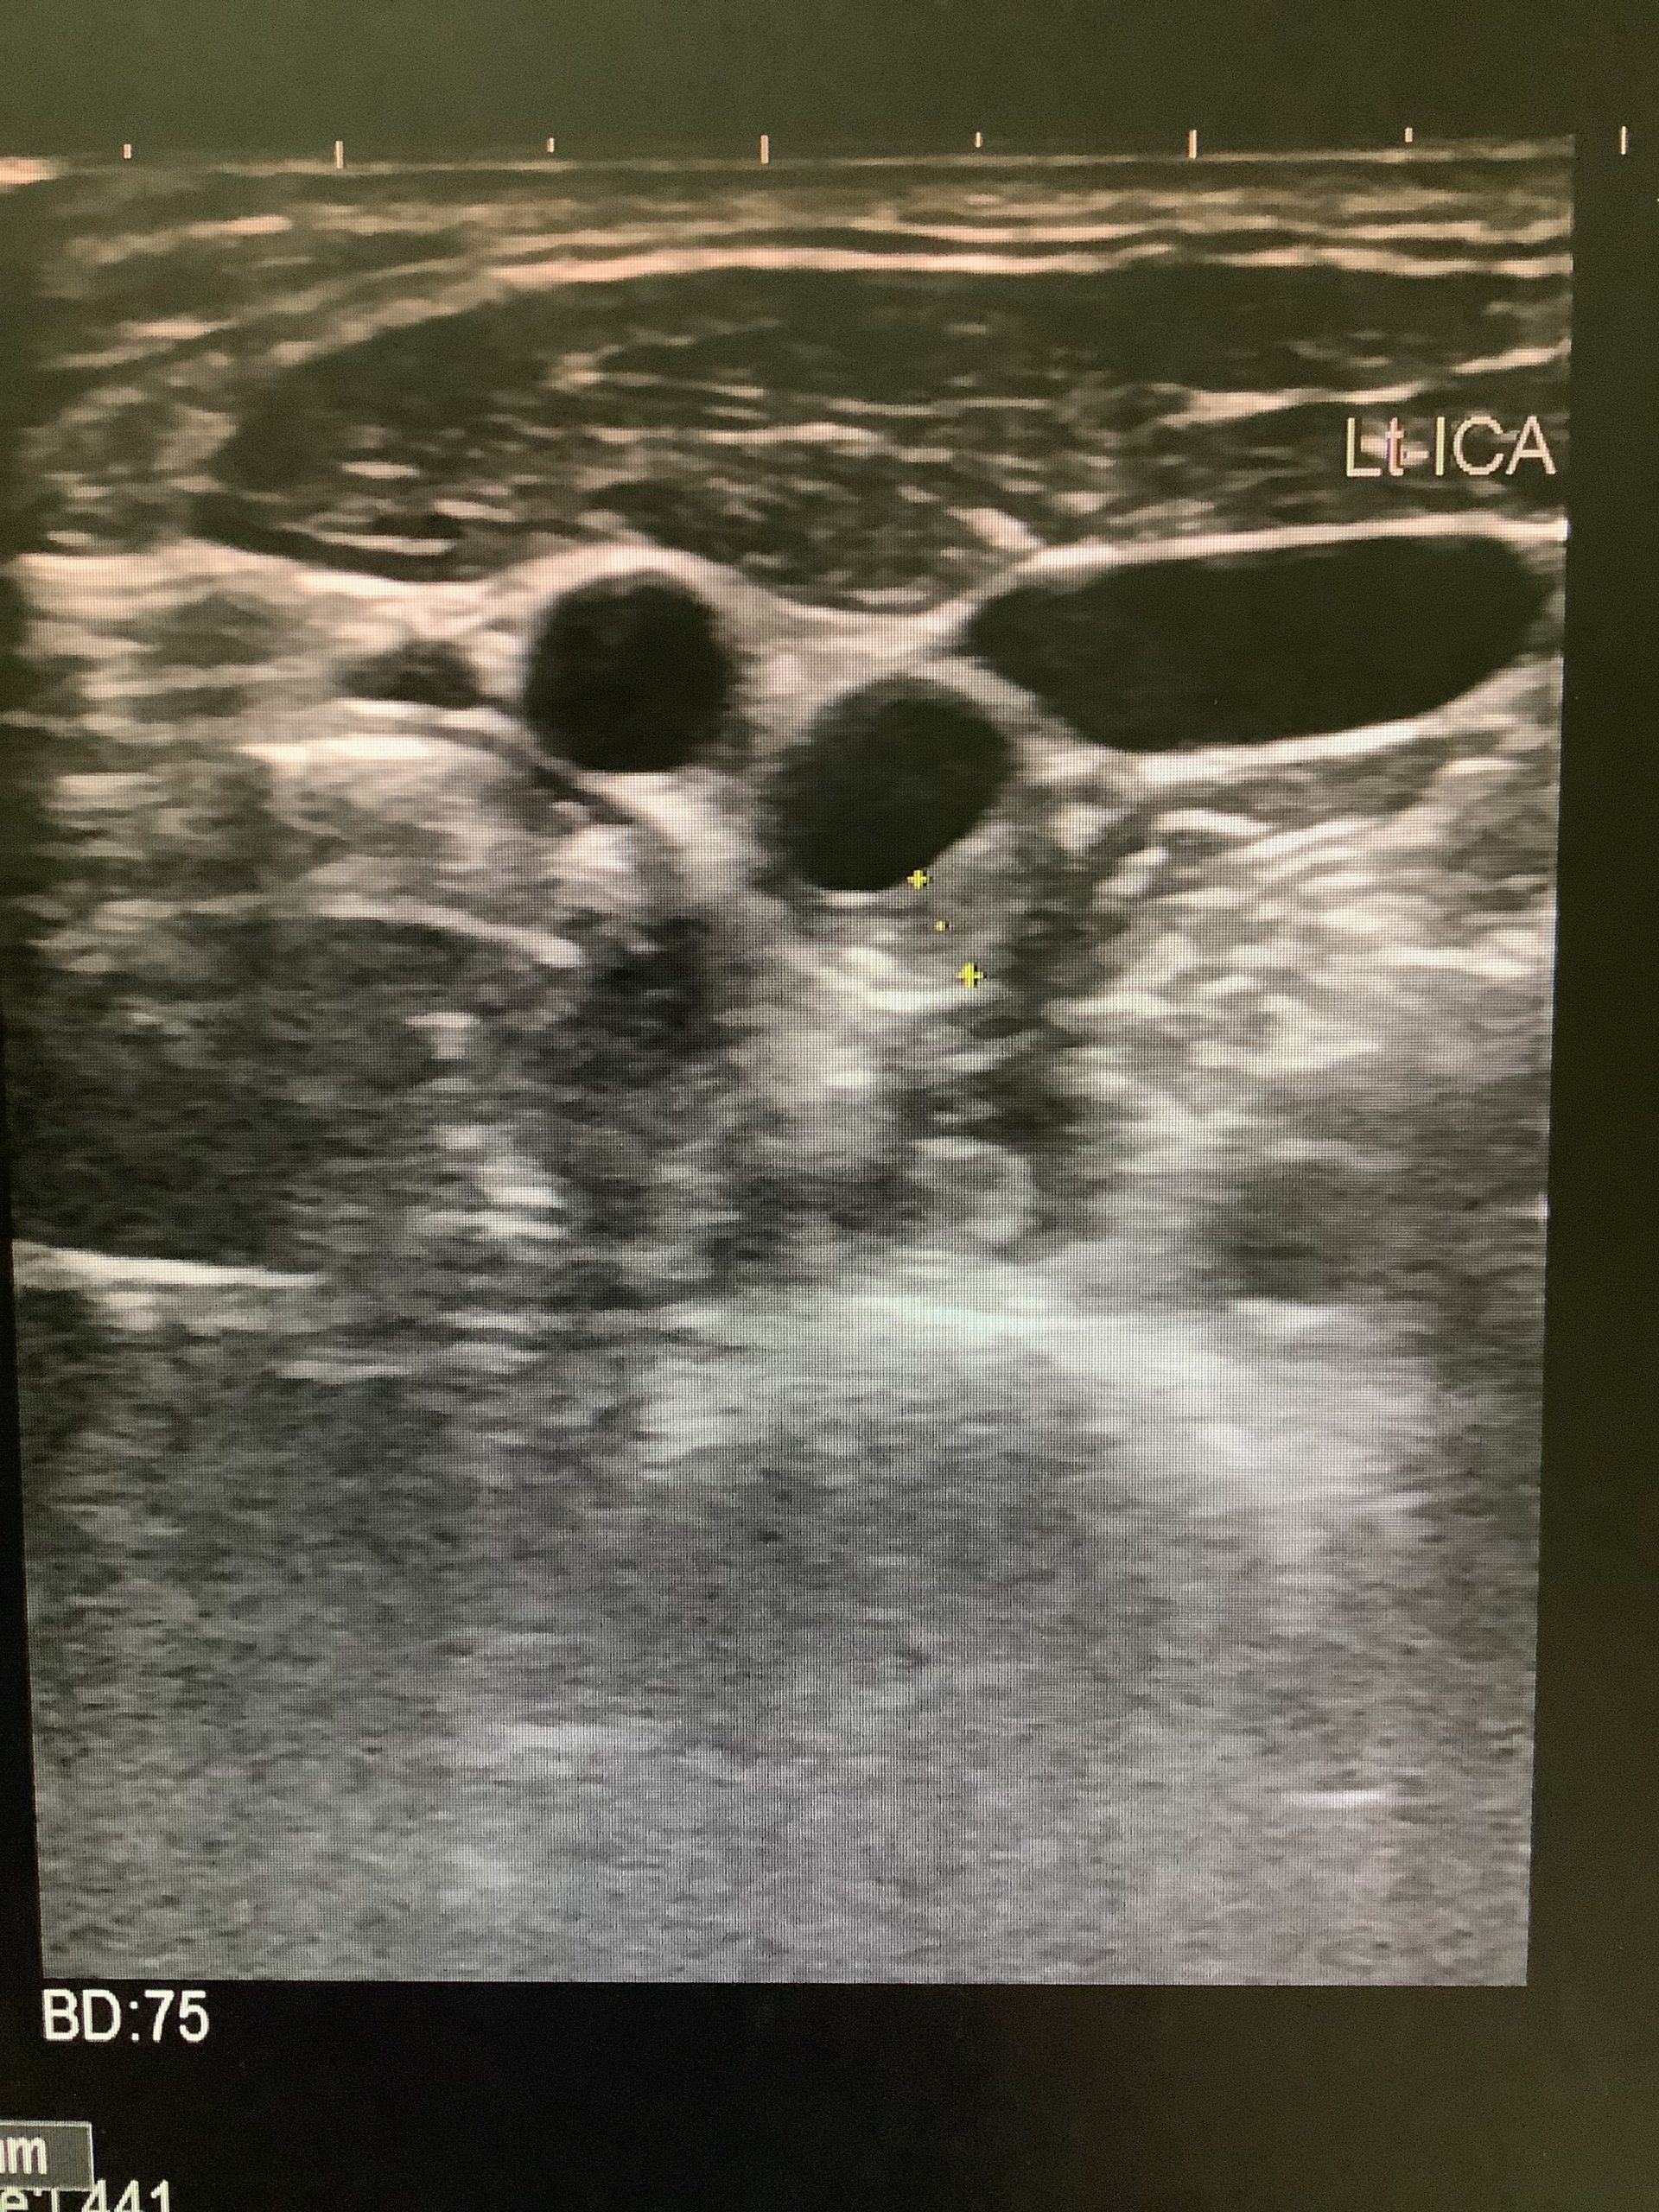

頸動脈エコー検査

今回は頸動脈エコーについてご紹介します。

頸動脈は脳に血液を送り込む血管です。

そのため、頸動脈の動脈硬化の有無、血管の詰まり具合、プラークの状態を調べることで、

心筋梗塞や脳梗塞のリスクが高いかどうかがわかります。